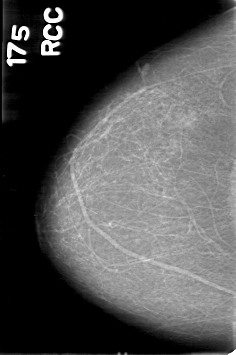

D_4028_1.RIGHT_CC

RIGHT_CC LINES 5311 PIXELS_PER_LINE 3526 BITS_PER_PIXEL 12 RESOLUTION 43.5 NON_OVERLAY